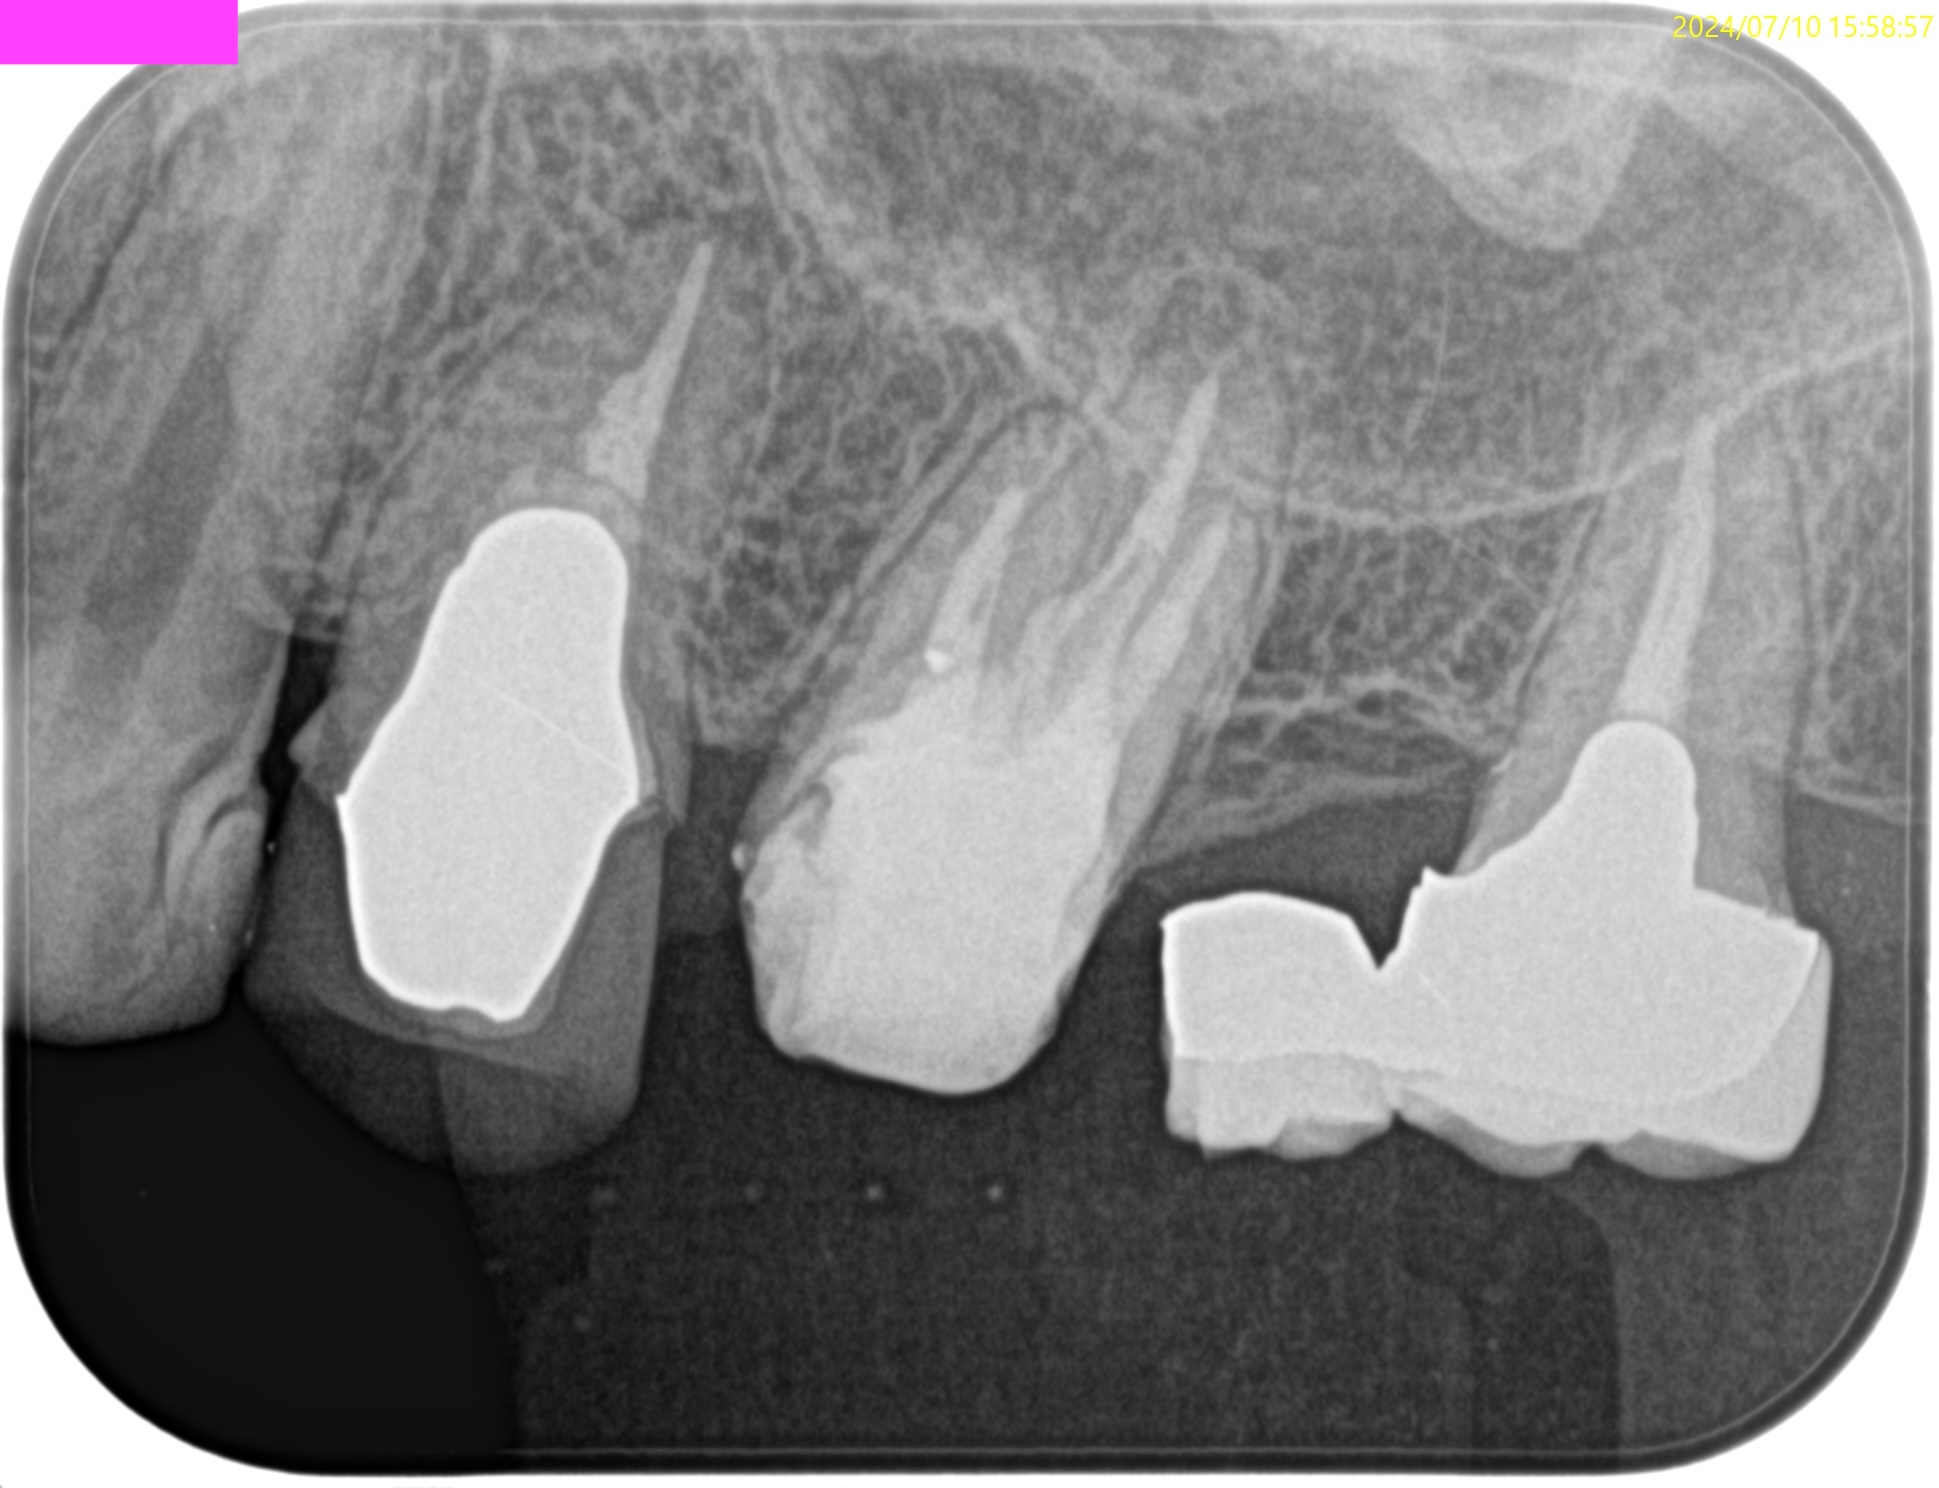

術後にPA, CBCTを撮影した。

#16

ここから1年、時間をおいた。

#3,14,16 Re-RCT 1yr recall(2025.10.20)

初診時+治療直後と比較した。

#3

#14

劇的に病気が治癒している。

特に#16は凄まじい。

超音波洗浄しかできなかったのに根尖病変が治癒しているのだ。

免疫力が非常に強い患者さんなのだろう。

あらためて、この話↓を実感せずにはいられない。

Siqueria 2008 Clinical implications and microbiology of bacterial persistence after treatment procedures

ということで、かかりつけ医には最終補綴を依頼した。